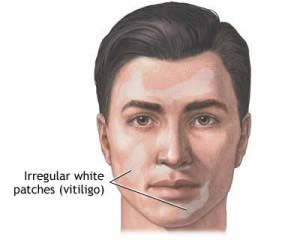

Hair & Beauty